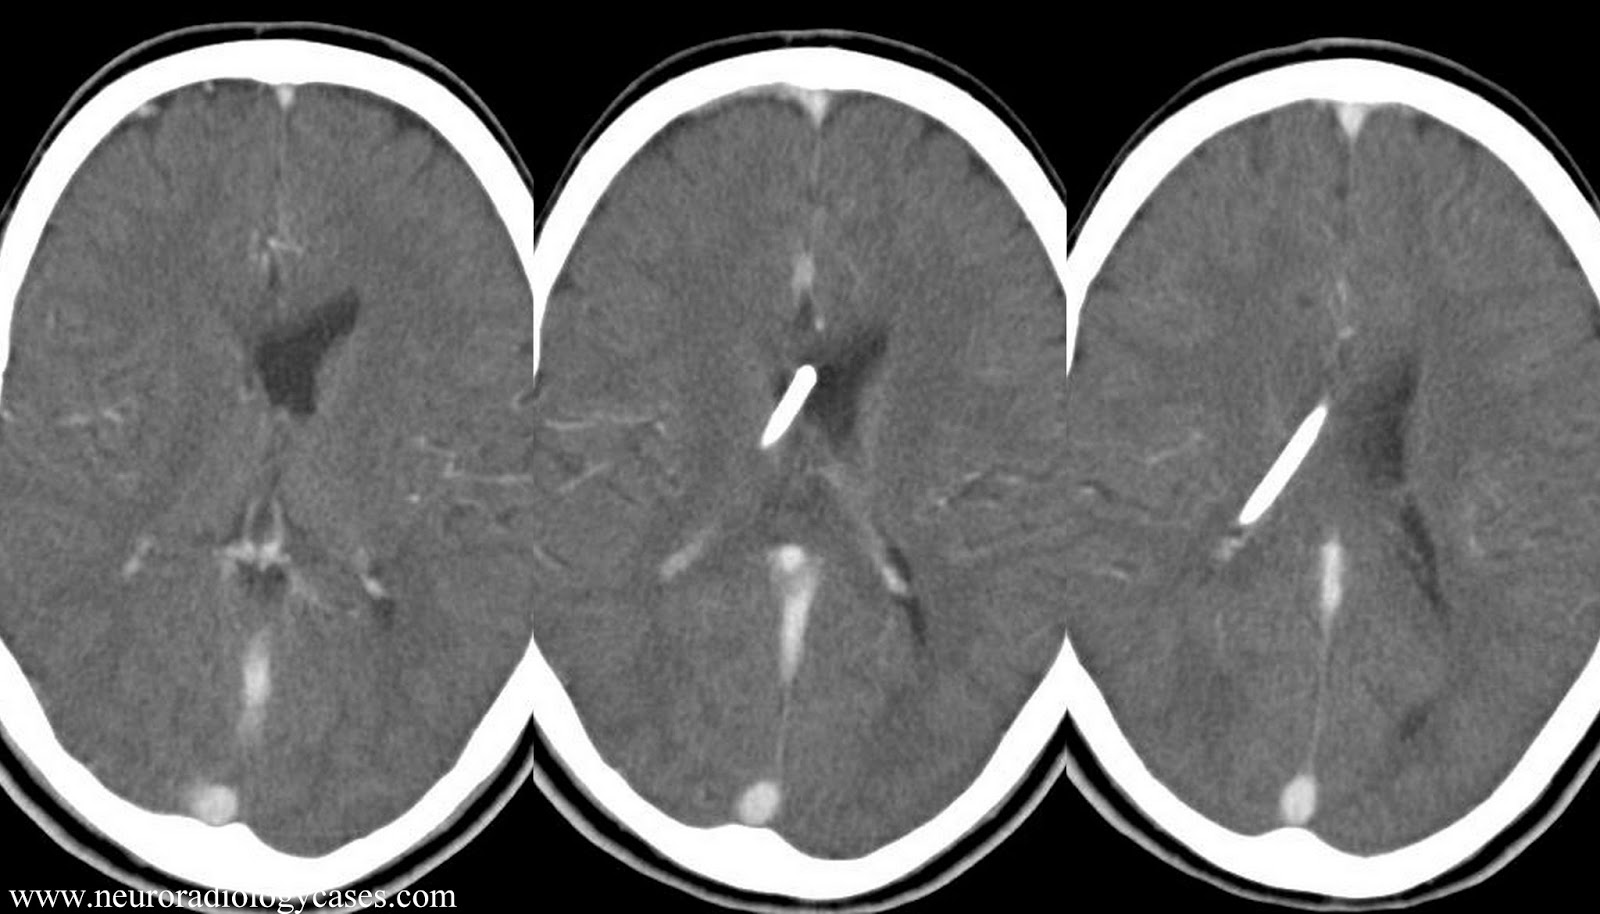

From www.neuroradiologycases.com

Dr Balaji Anvekar FRCR CSF shunt imaging Shunt Reset After Mri Contact your care provider before you schedule an mri. the main risk of mri is unintentional resetting of the valve pressure. while programmable shunts are generally mri compatible up to 3t, there is a potential risk for inadvertent change of settings during mri. you have an mri for any reason (ct scans have no effect on the. Shunt Reset After Mri.